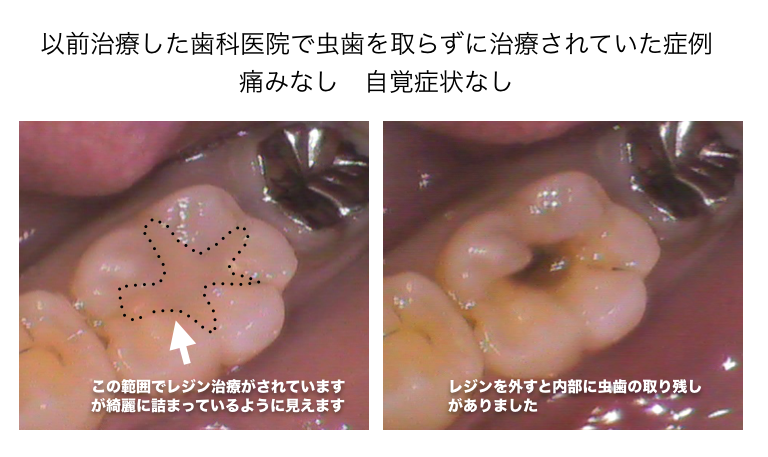

CASE1

以前治療したレジン治療の内部から虫歯の取り残しが見つかった症例

レジン治療の内部で虫歯の取り残しがあった症例